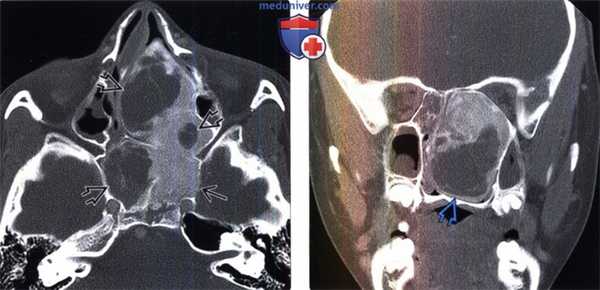

(Слева) КТ, костное окно, аксиальный срез: у девятилетней пациентки наблюдается кистозный вариант фиброзной диспла -зии. Обратите внимание на зоны явной кистозной трансформации в области более характерных изменений по типу «матового стекла» и в смежных с ними отделах.

(Справа) КТ, костный режим, корональный срез: у этой же пациентки определяется экспансивная фиброзная дисплазия (ФД) носорешетчатой области; поражения имеют кистозные структуры, которые характеризуются тонкими, но скперозированными стенками..